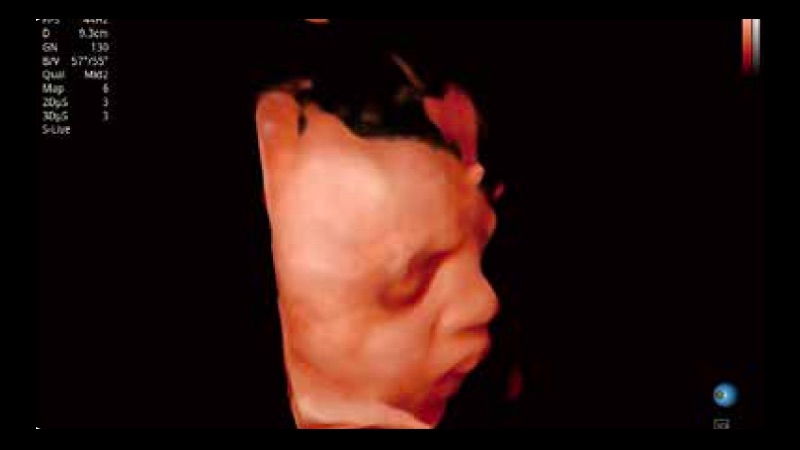

S-Fetus 产科扫查助手

S-Fetus基于大数据深度学习算法,能够帮助您在产前筛查过程中智能识别胎儿标准切面、自动测量并录入报告。一个按键,即可智能、精准、高效地获取胎儿生理指标,极大简化您的产科检查操作。